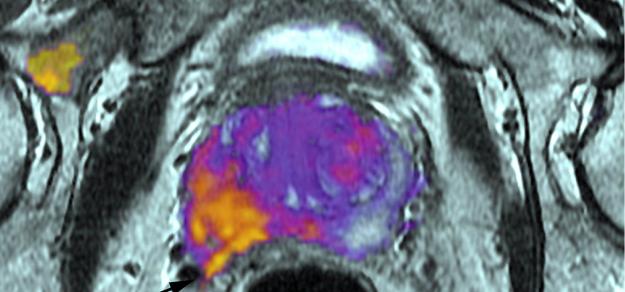

Debido al riesgo de acumulación de gadolinio, saldrán del mercado a partir de febrero de 2018 los contrastes para resonancia magnética que contienen gadodiamida (Omniscan®) y ácido gadopentético (Magnevist®). National Health Service, 13 de diciembre de 2017